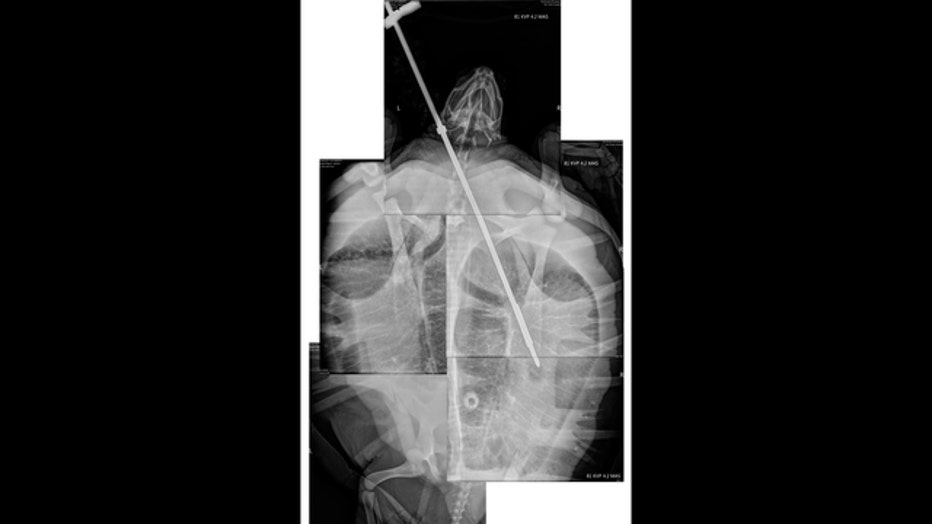

"X-rays revealed the spear went much deeper than the turtle’s neck, it spanned over half of its body," the hospital told Fox 35.